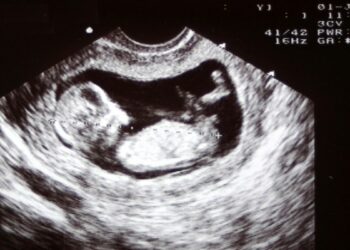

Spain: Supreme Court condemns abortion centers for misleading advertisements that conceal after-effects of abortion

The Supreme Court confirms the sentence of the Provincial Court of Oviedo that condemned ACAI, the employers' association that groups ...